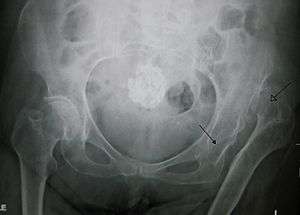

Congenital dislocation of the left hip. Closed arrow marks the acetabulum, open arrow the femoral head.

Congenital hip dislocation must be detected early when it can be easily treated by a few weeks of traction. If it is not detected, the child's hip may develop incorrectly, seen when the child begins to walk. If one hip is affected the child will have a limp and lurch and with bilateral dislocation there will be a waddling gait. On physical exam, with the baby in the supine position, the examiner flexes both the hips and knees to 90 degrees, and, holding the knees, pushes gently downward, which may induce a posterior dislocation or subluxation. Keeping the baby in this 90 degree flexed position, the examiner then externally rotates the thighs. A normal infant will demonstrate no evidence of dislocation. It can also be detected with the Galeazzi test. Congenital hip dislocation is much more common in girls than boys.

X-Ray Photo of post surgery hip dislocation.